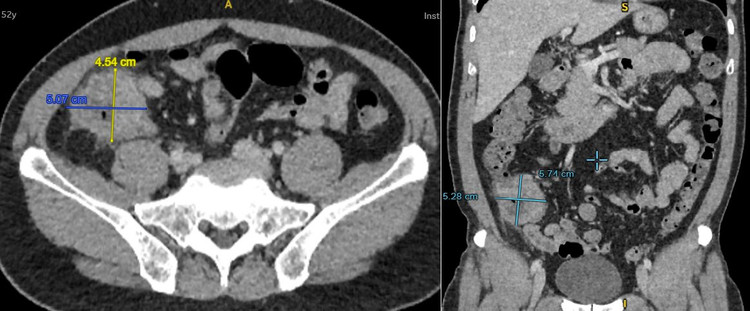

Bệnh nhân là ông L.H. T (52 tuổi, Bình Thuận), nhập viện trong tình trạng đau âm ỉ vùng hố chậu phải. Tại Khoa Cấp Cứu BVĐK Xuyên Á, người bệnh được thăm khám, chỉ định chụp CT - scanner bụng phát hiện khối u manh tràng kích thước lớn 05x06 cm, di căn hạch, nội soi đại tràng phát hiện manh tràng có khối u sùi bề mặt nham nhở, dễ xuất huyết, chiếm gần hết lòng manh tràng. Sau sinh thiết, kết quả ghi nhận đây là ung thư biểu mô tuyến ở đại tràng, biệt hoá vừa.

| Biểu hiện của khối u trên phim chụp - Ảnh BVCC |